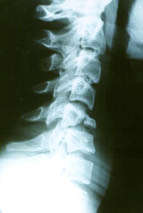

Pédagogie Spondylolyse & Spondylolisthésis isthmique chez l’adulte , Frédéric Jacquot Pôle Appareil Locomoteur, Hôpital Saint Antoine, 184 rue du Faubourg Saint Antoine, 75012 Paris, France N°230 - Janvier 2014 ● 35 min de lecture